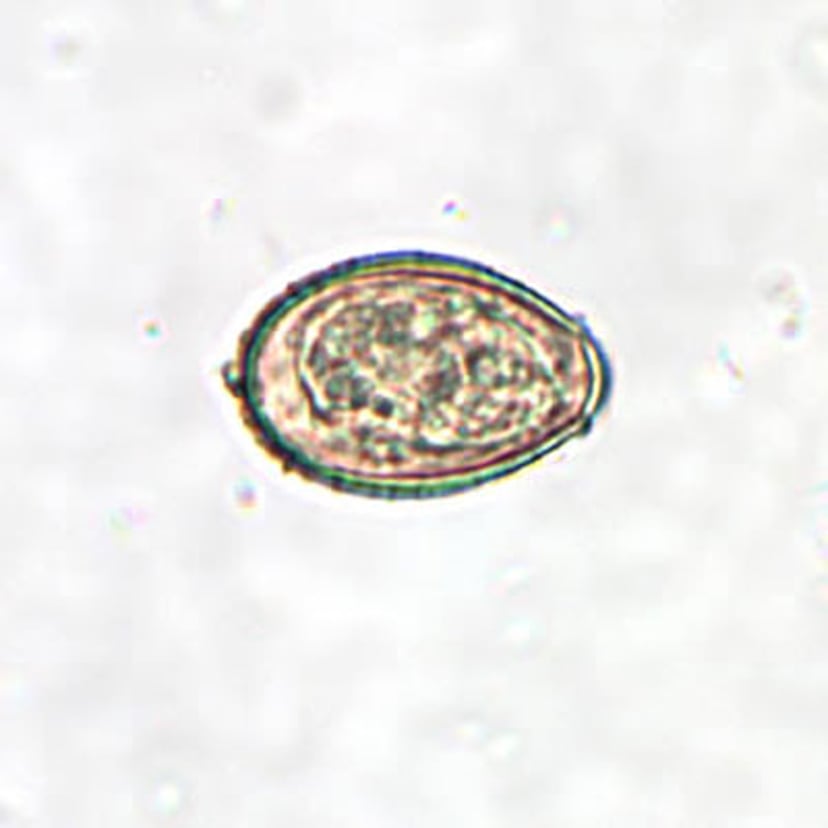

Huevo de Clonorchis sinensis

Los huevos de C. sinensis son pequeños, con un tamaño que varía de 27 a 35 micrómetros por 11 a 20 micrómetros. Los huevos son de forma ovalada con un opérculo convexo (cubierta protectora o estructura similar a una tapa) que descansa sobre "hombros" visibles en el extremo más pequeño del huevo. Ampliación 400X.